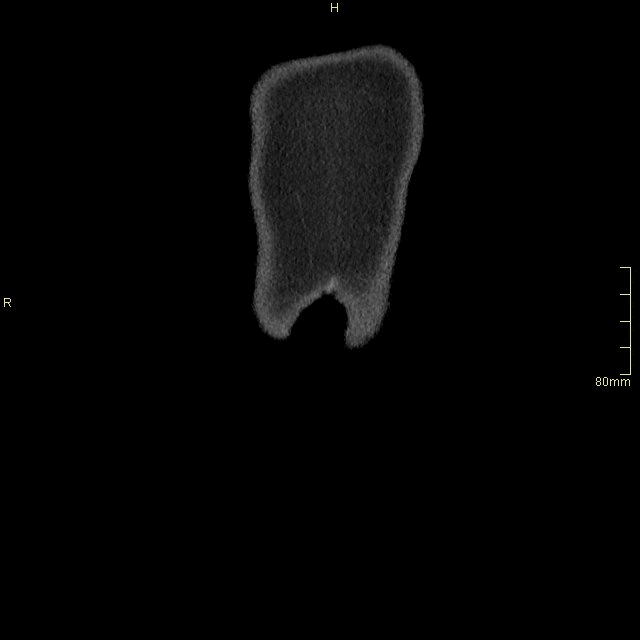

CT Abdomen/Pelvis - Non Contrast Coronal